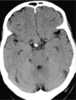

Suprasellar neoplasm

A craniopharyngioma is a rare type of brain tumor derived from pituitary gland embryonic tissue that occurs most commonly in children, but also affects adults. It may present at any age, even in the prenatal and neonatal periods, but peak incidence rates are childhood-onset at 5–14 years and adult-onset at 50–74 years. [Source: Wikipedia ]